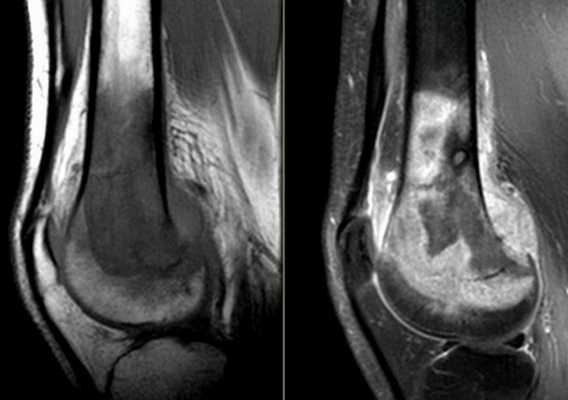

Остеосаркома бедренной кости на снимке коленного сустава

КТ колена

С помощью компьютерной томографии визуализируют нарушения связочного аппарата, костных суставных поверхностей, гиалинового хряща, синовиальной оболочки и капсулы сочленения. Ограничение подвижности и боль возникают чаще при травмах, воспалительных и дегенеративных патологиях.

КТ коленного сустава позволяет диагностировать хондромаляции (разрушение хряща), повреждения менисков, разрывы крестообразных связок. В результате контрастной процедуры выявляют онкологические процессы, заболевания сосудов, липоартрит и пр.